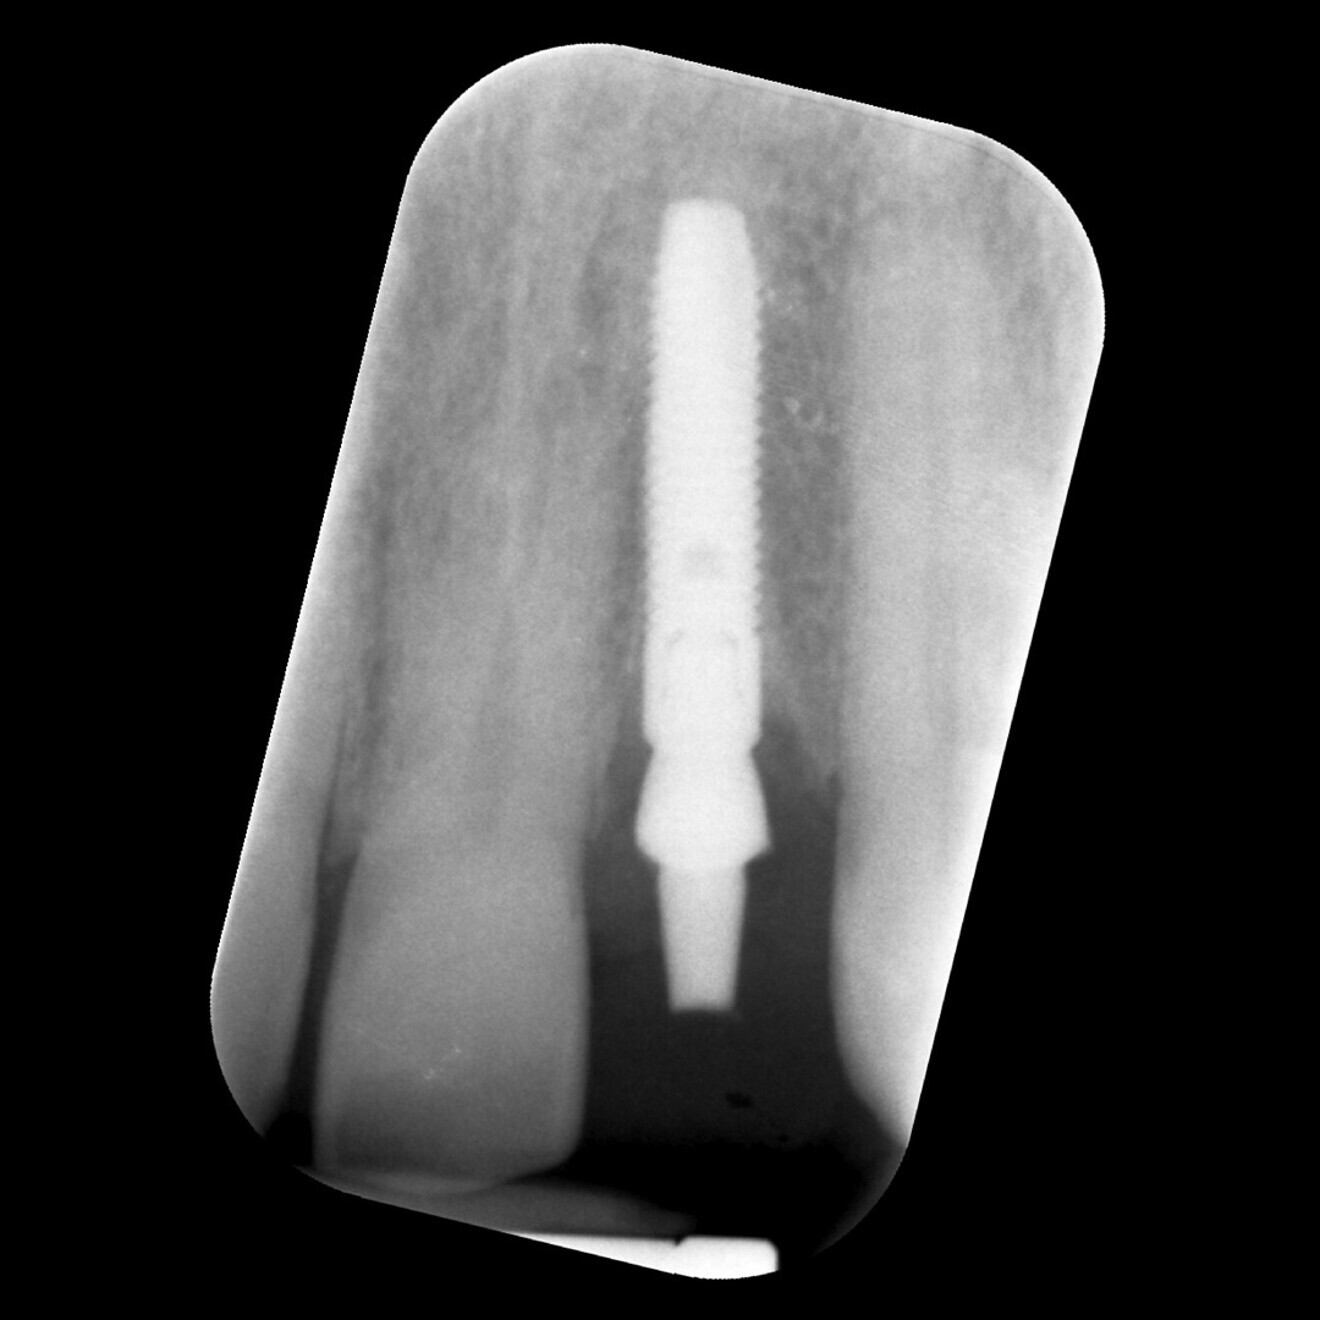

Fig. 16: Baseline radiograph of the implant mapped in Figure 15, showing good marginal bone levels.

For another patient, the implant was seen to dramatically reduce in ISQ values from a baseline of 72/74 to 56/58 at the three-month postoperative review, even though the implant was immobile and was resistant to manual torque without pain (Fig. 15). However, a simple intra-oral radiograph confirmed that, compared with baseline (Fig. 16), there was significant loss of crestal bone (Fig. 17), thus corroborating the significance of the drop in ISQ values.